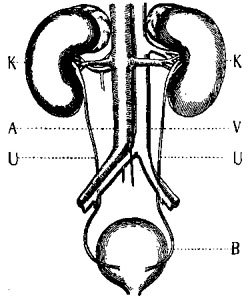

200 The Urinary System

These cells are always actively at work picking out the substances they need, and manufacturing out of them the ferments and acids, or alkalies, needed for acting upon the food in their particular part of the tube, whether it be the mouth, the stomach, or the small intestine.